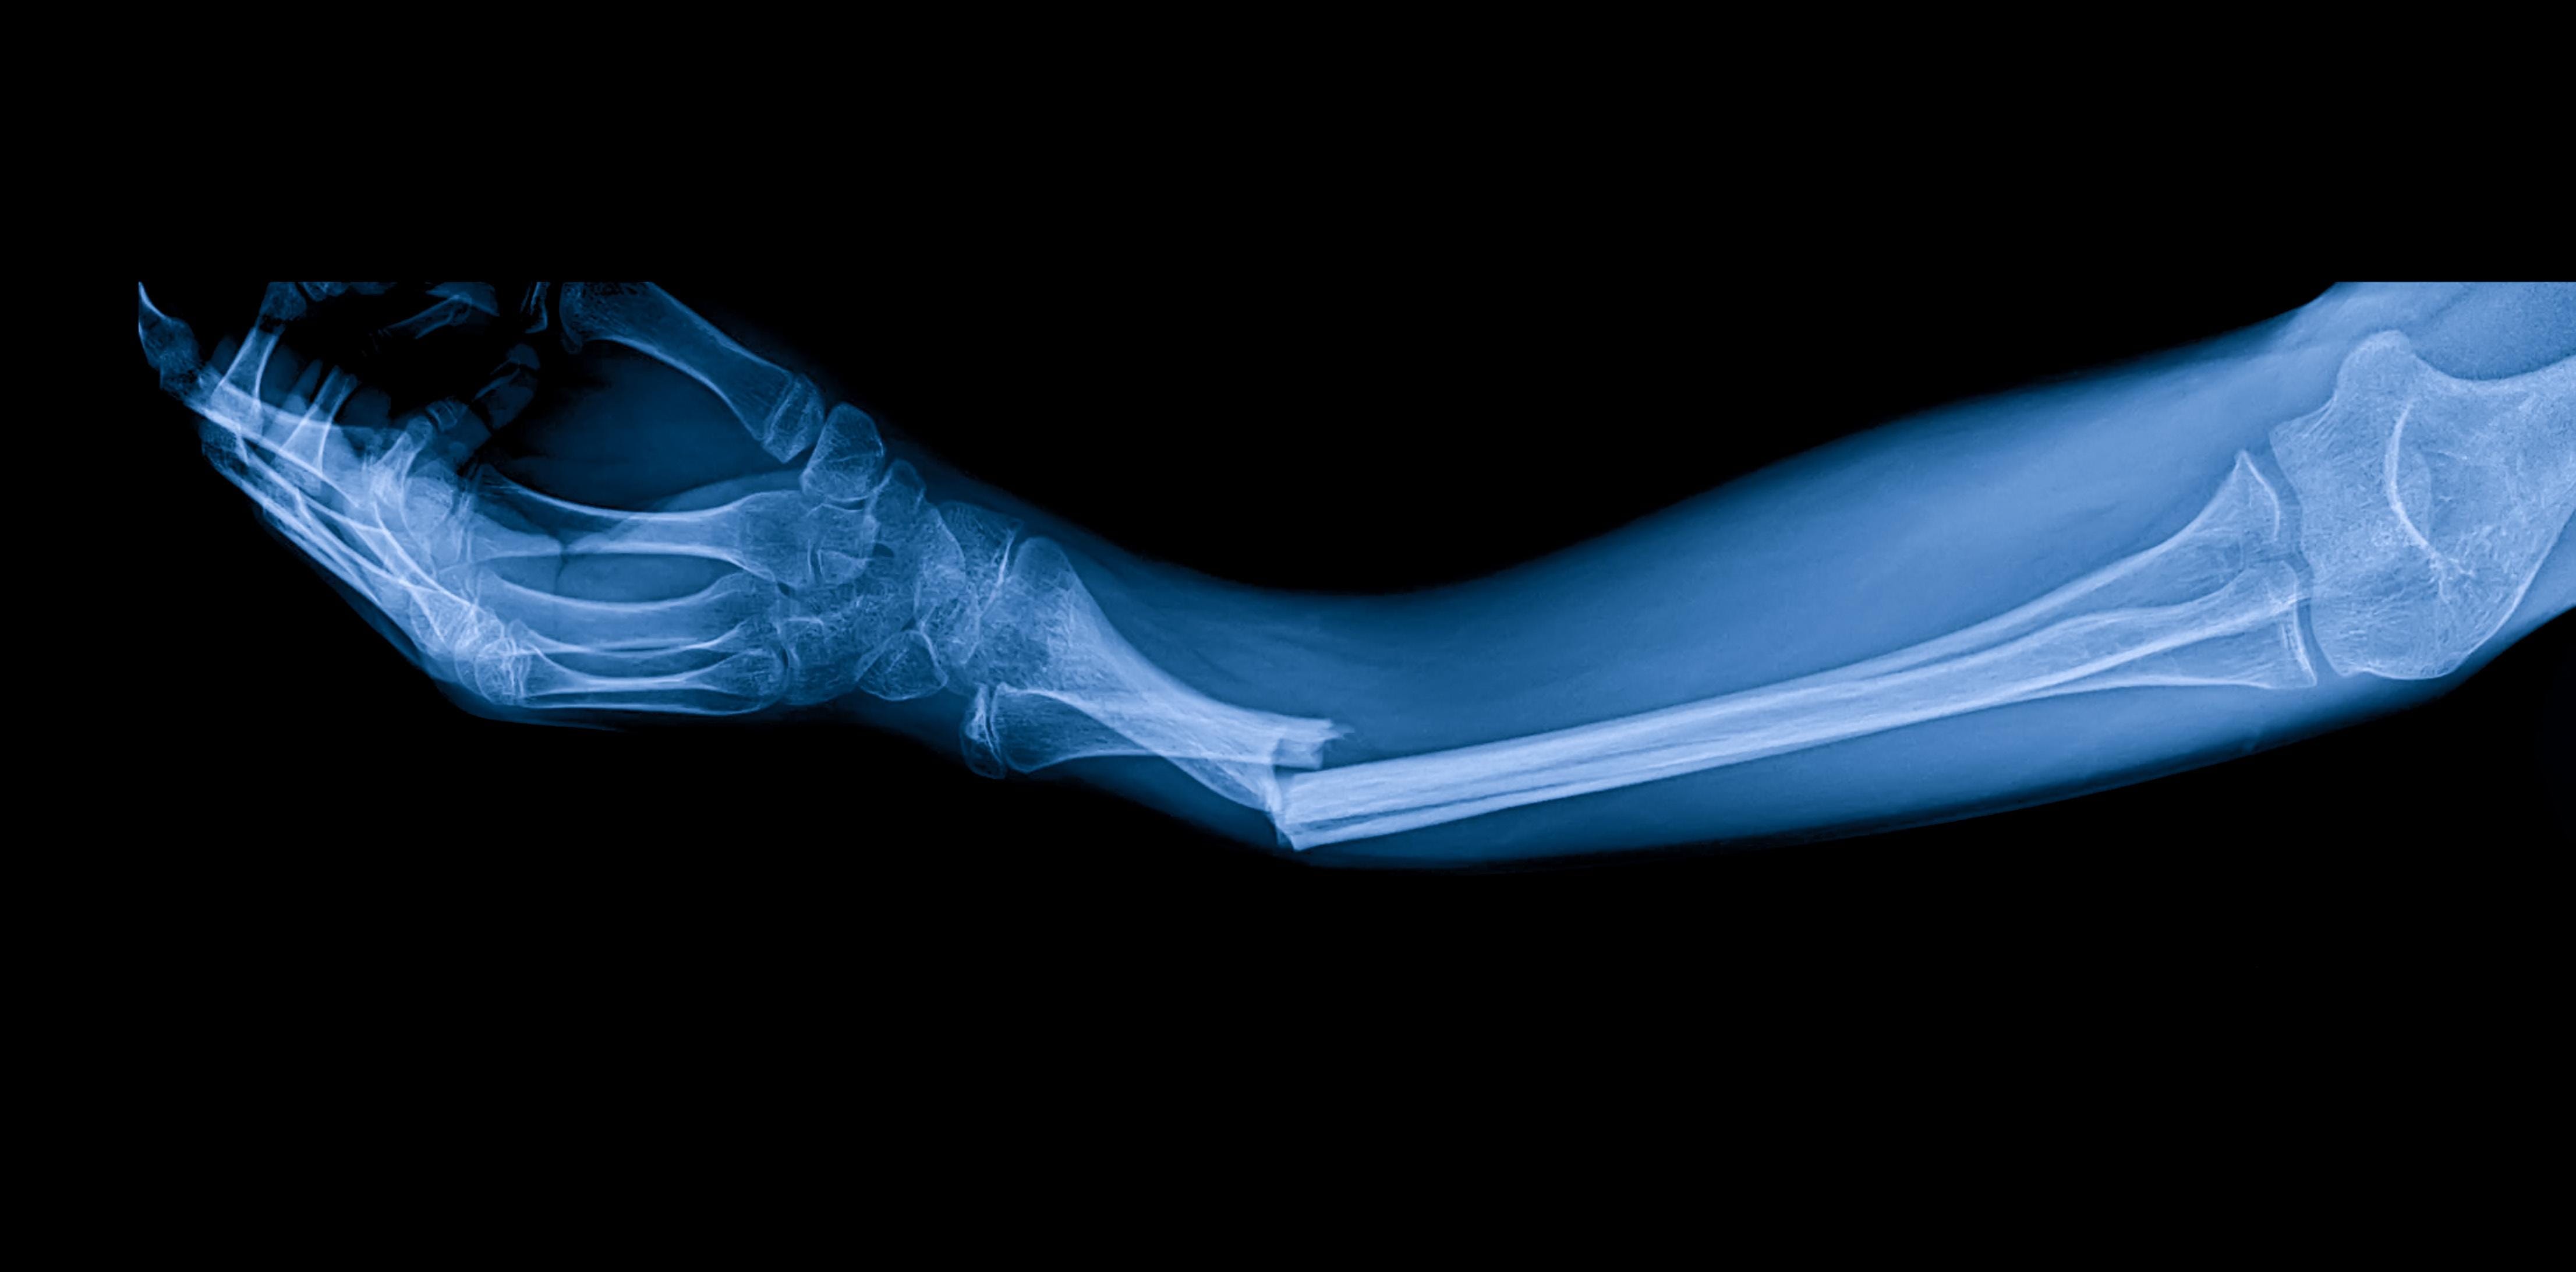

In an unprecedented scientific advance in orthopedics, a team of Chinese researchers led by Dr. Lin Xianfeng in Zhejiang Province has developed an innovative bone glue called Bone-02, capable of joining broken bone fragments in just three minutes without the need for metal plates or screws. This biomimetic adhesive, inspired by oysters’ ability to firmly adhere in wet environments, can fix fractures even in surgical settings with abundant blood, a challenge for medical adhesives until now…..

Its application requires only a minimal incision, and the glue is directly introduced into the fractured area, sealing bone fragments in minutes. Moreover, Bone-02 is biodegradable, absorbing naturally as the bone structure regenerates, eliminating the need for secondary surgery to remove plates or screws, significantly reducing infection risks and recovery times.